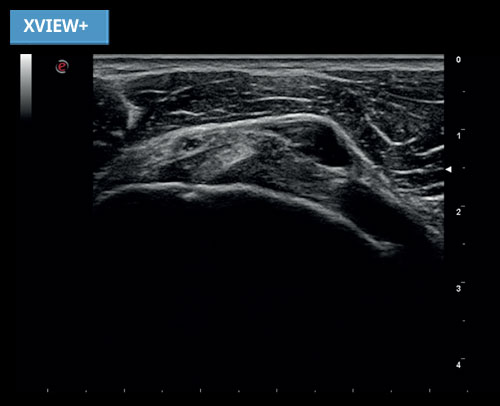

Redukce skvrn artefaktů je velmi důležitá funkce. Uživatelé si musí být jisti typem zobrazování, které mohou získat pomocí ultrazvukového systému. Z tohoto důvodu má nová adaptivní technologie XView + redukce skvrn také funkci vyvážení, kterou mohou operátoři použít k přizpůsobení chování algoritmu podle svých preferencí.